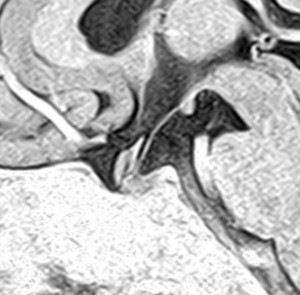

増大しても下垂体症状を出さなかった例

9歳の女の子に偶然発見された腫瘍です。何の症状もありませんでした。頭蓋咽頭腫と診断されて経過観察となりました。1年半観察しましたが腫瘍は増大して,視交差の変形が増して両耳側1/4半盲となり症候性となりました。下垂体機能は正常でした。

上のT2強調画像では,全体的に低信号で,高信号の部分が混在します。上右のCISS画像では,下垂体組織が右に変移していることが推定されます。

左がT1強調画像で高信号,右がT1ガドリニウム増強像ですが腫瘍は増強されません。正常か錐体が腫瘍の右側にくっついていて,ガドリニウム増強されています。典型的なトルコ鞍部黄色肉芽腫です。画像診断で,下垂体腺腫の腫瘍内出血とよく間違われるのですが,高信号になるのはコレステリン結晶を豊富に含むからです。ガドリニウム増強される部分がほとんどないという所見が頭蓋咽頭腫とは異なるところでしょう。

左と中央の画像でinfundibular recessの管腔が見え,左の視交差から視索の変形が強いことが解ります。右の画像では下垂体組織がトルコ鞍の右側に偏在してあります。画像では正常化錐体と明瞭な境界があるように見えるのですが,実際の手術所見では正常下垂体との境界は不鮮明でした。腫瘍のう胞からは黒褐色の内容液 machinery oil とコレステリン結晶が流出しました。厚いのう胞壁は硬膜と下垂体に強く付着して剥離するのが困難で切断して摘出しました。ラトケのう胞とはのう胞壁の厚さが異なると言えます。